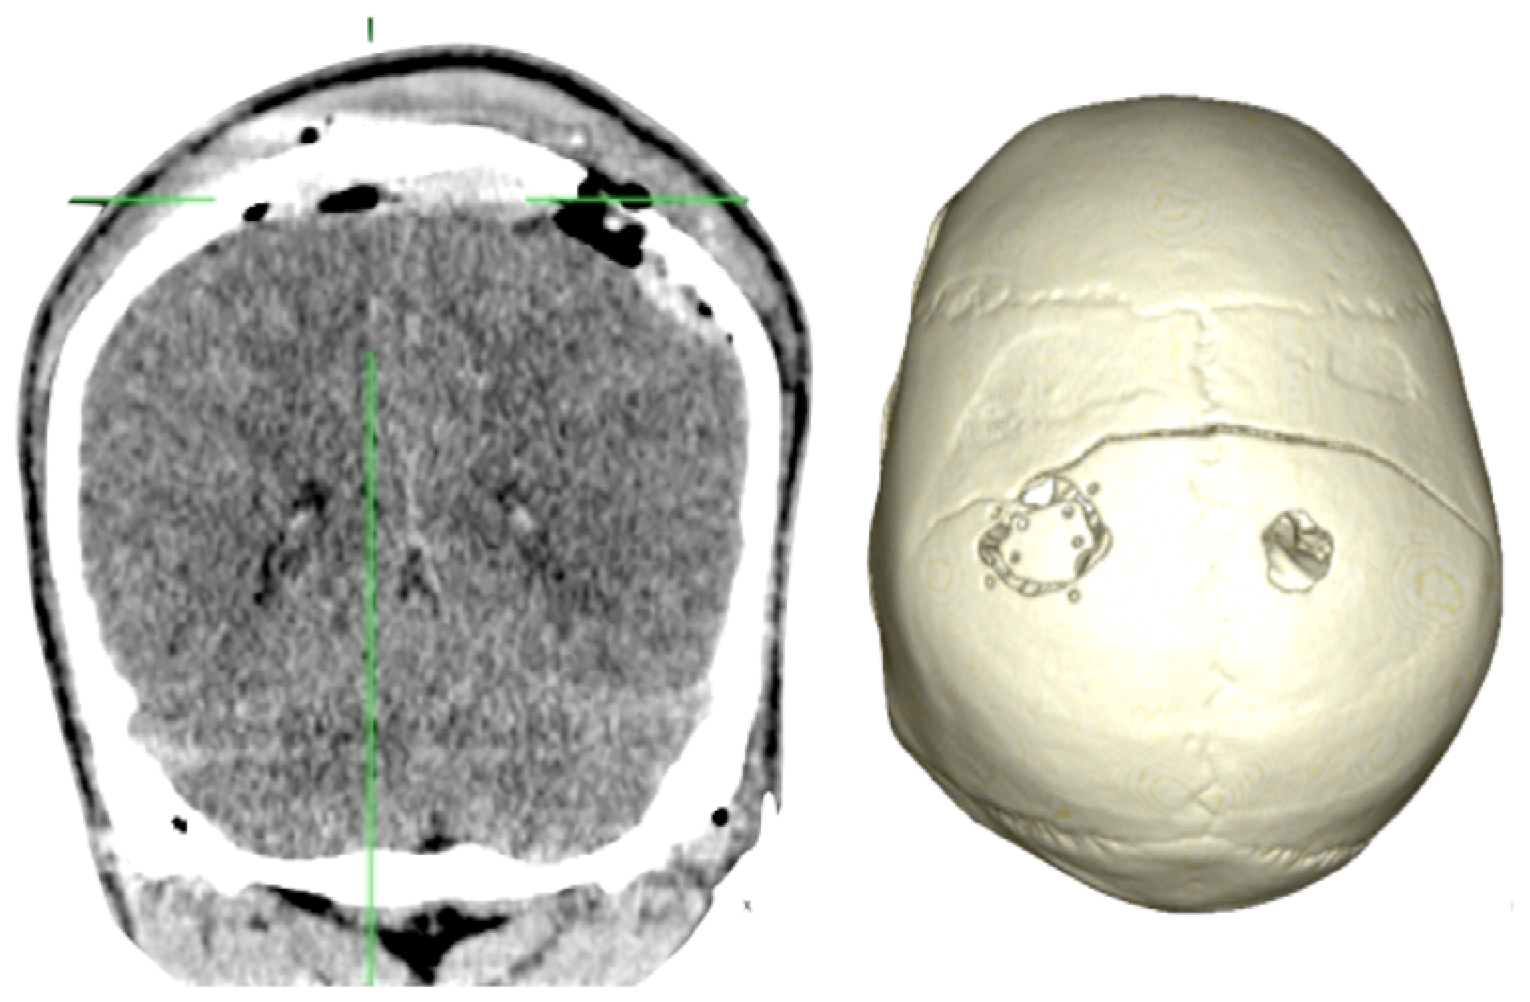

Case 1-Epidural Hematoma (See Figures 1 and 2 for the details)

A 48-year-old male patient experienced traumatic brain injury due to fall from a height of 3 m. Initial loss of consciousness was noted, but the patient remained conscious and alert after the insult. He went home and was found drowsy by a family member. He was then brought to our emergency department (GCS of 14), where head CT scan revealed a bilateral parietal EDH (40 mL in volume).

The 3D reconstruction enabled a minimally invasive approach to this case. A linear incision was made at the site where the center of the hematoma is located, and a 2.5-cm diameter craniotomy was created. Another 1.5 cm incision and 1 cm burr-hole was performed in the contralateral side, leaving the hematoma beneath the superior sagittal sinus untouched. After surgery the patient had an excellent recovery with no neurological deficits. He was discharged three days after admission to the hospital.